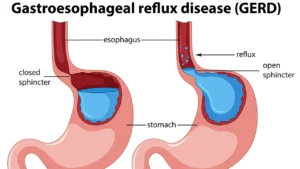

قبل التطرق إلى اسباب الاكاليزيا، من المهم فهم طبيعة هذا المرض. الأكاليزيا هي اضطراب نادر يصيب العضلة العاصرة السفلية للمريء، مما يمنعها من الاسترخاء بشكل طبيعي أثناء البلع. هذا يؤدي إلى تراكم الطعام في المريء وصعوبة في البلع تُعرف باسم عسر البلع.

يصيب هذا المرض حوالي شخص واحد من كل 100,000 شخص سنوياً، ويمكن أن يحدث في أي عمر، لكنه أكثر شيوعاً بين البالغين في منتصف العمر. تشمل الأعراض الرئيسية صعوبة البلع، ألم الصدر، وارتجاع الطعام غير المهضوم.